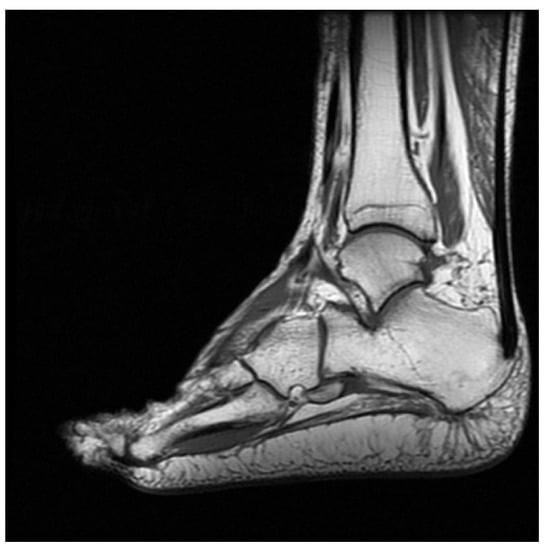

2. Case Presentation